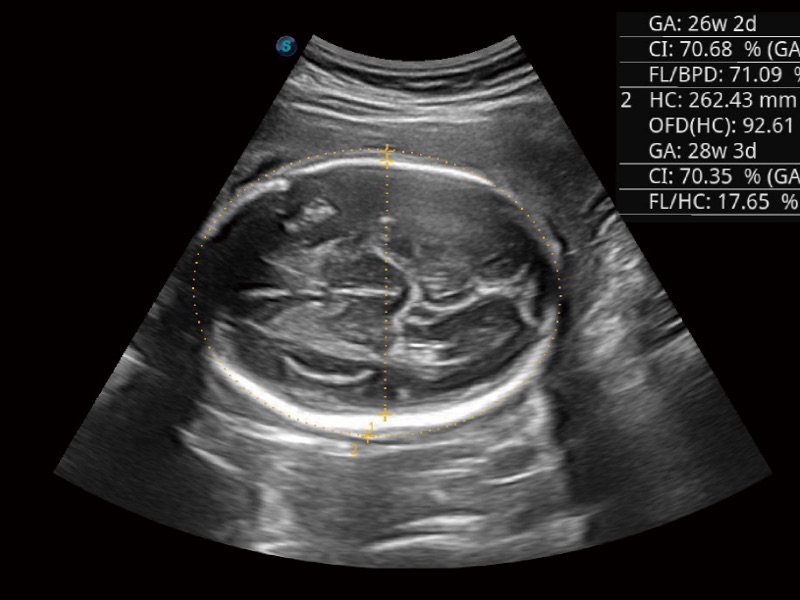

妇产科应用